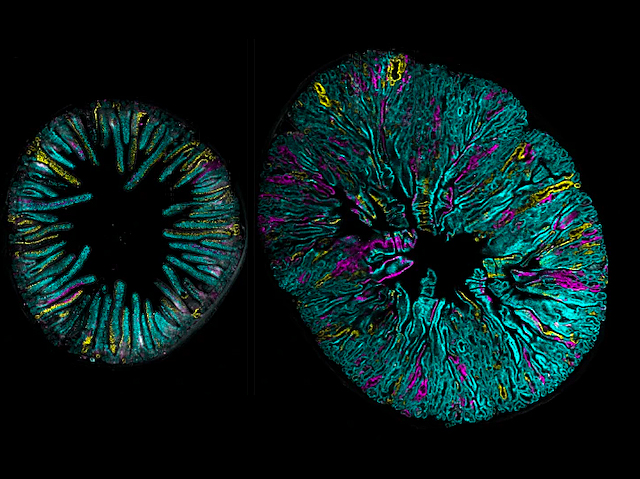

Desenvolupament Inexpressiu+

Desenvolupament Inexpressiu+27 de setembre de 2016